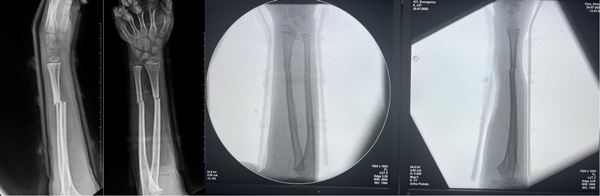

县人民医院骨科团队对其伤情进行全面评估后,与其家属共同选择了“放弃手术”,以采用手法复位闭合治疗加外固定术为患儿采取保守治疗。医护团队在C臂透视机引导下,凭借丰富经验与娴熟技巧,精准完成骨折端的对位对线,并实施夹板外固定,影像显示,骨折对位对线良好,达到功能复位标准。

术中复位透视